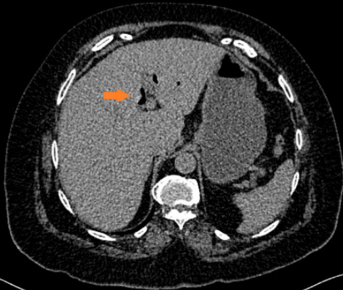

Laboratory tests showed electrolyte imbalance in 14 patients (87.5%) and liver function tests abnormalities in five patients (31.2%). A correct preoperative diagnosis of GI was reached in 13 patients (81.2%); the remaining was diagnosed during surgery. The classical image signs of GI were visualized in 7 patients (43.7%) on plain abdominal radiograph (Figure 1), in six patients (37.5%) on ultrasound (Figure 2) (Figure 3), and in 13 patients (81.2%) on CT (Figure 4) (Figures 5a & b).

Figure 5A & 5B Oral contrast-enhanced computed tomography findings in a patient with gallstone ileus. a. Gas observed within the gallbladder (arrow) b. Communication between a non-distended gallbladder and the duodenum, where presence of oral contrast is observed in the site of the fistula (arrow), and fluid-filled dilated jejunal loops and intestinal pneumatosis (arrowhead).

Image findings included radio-opaque image suggestive of a gallstone in 11 patients (68.7%), (Figure 6) bowel distention in 10 patients (62.5%) (Figure 7), and pneumobilia in 8 patients (50%) (Figure 8), all classical signs of Rigler´s triad.7